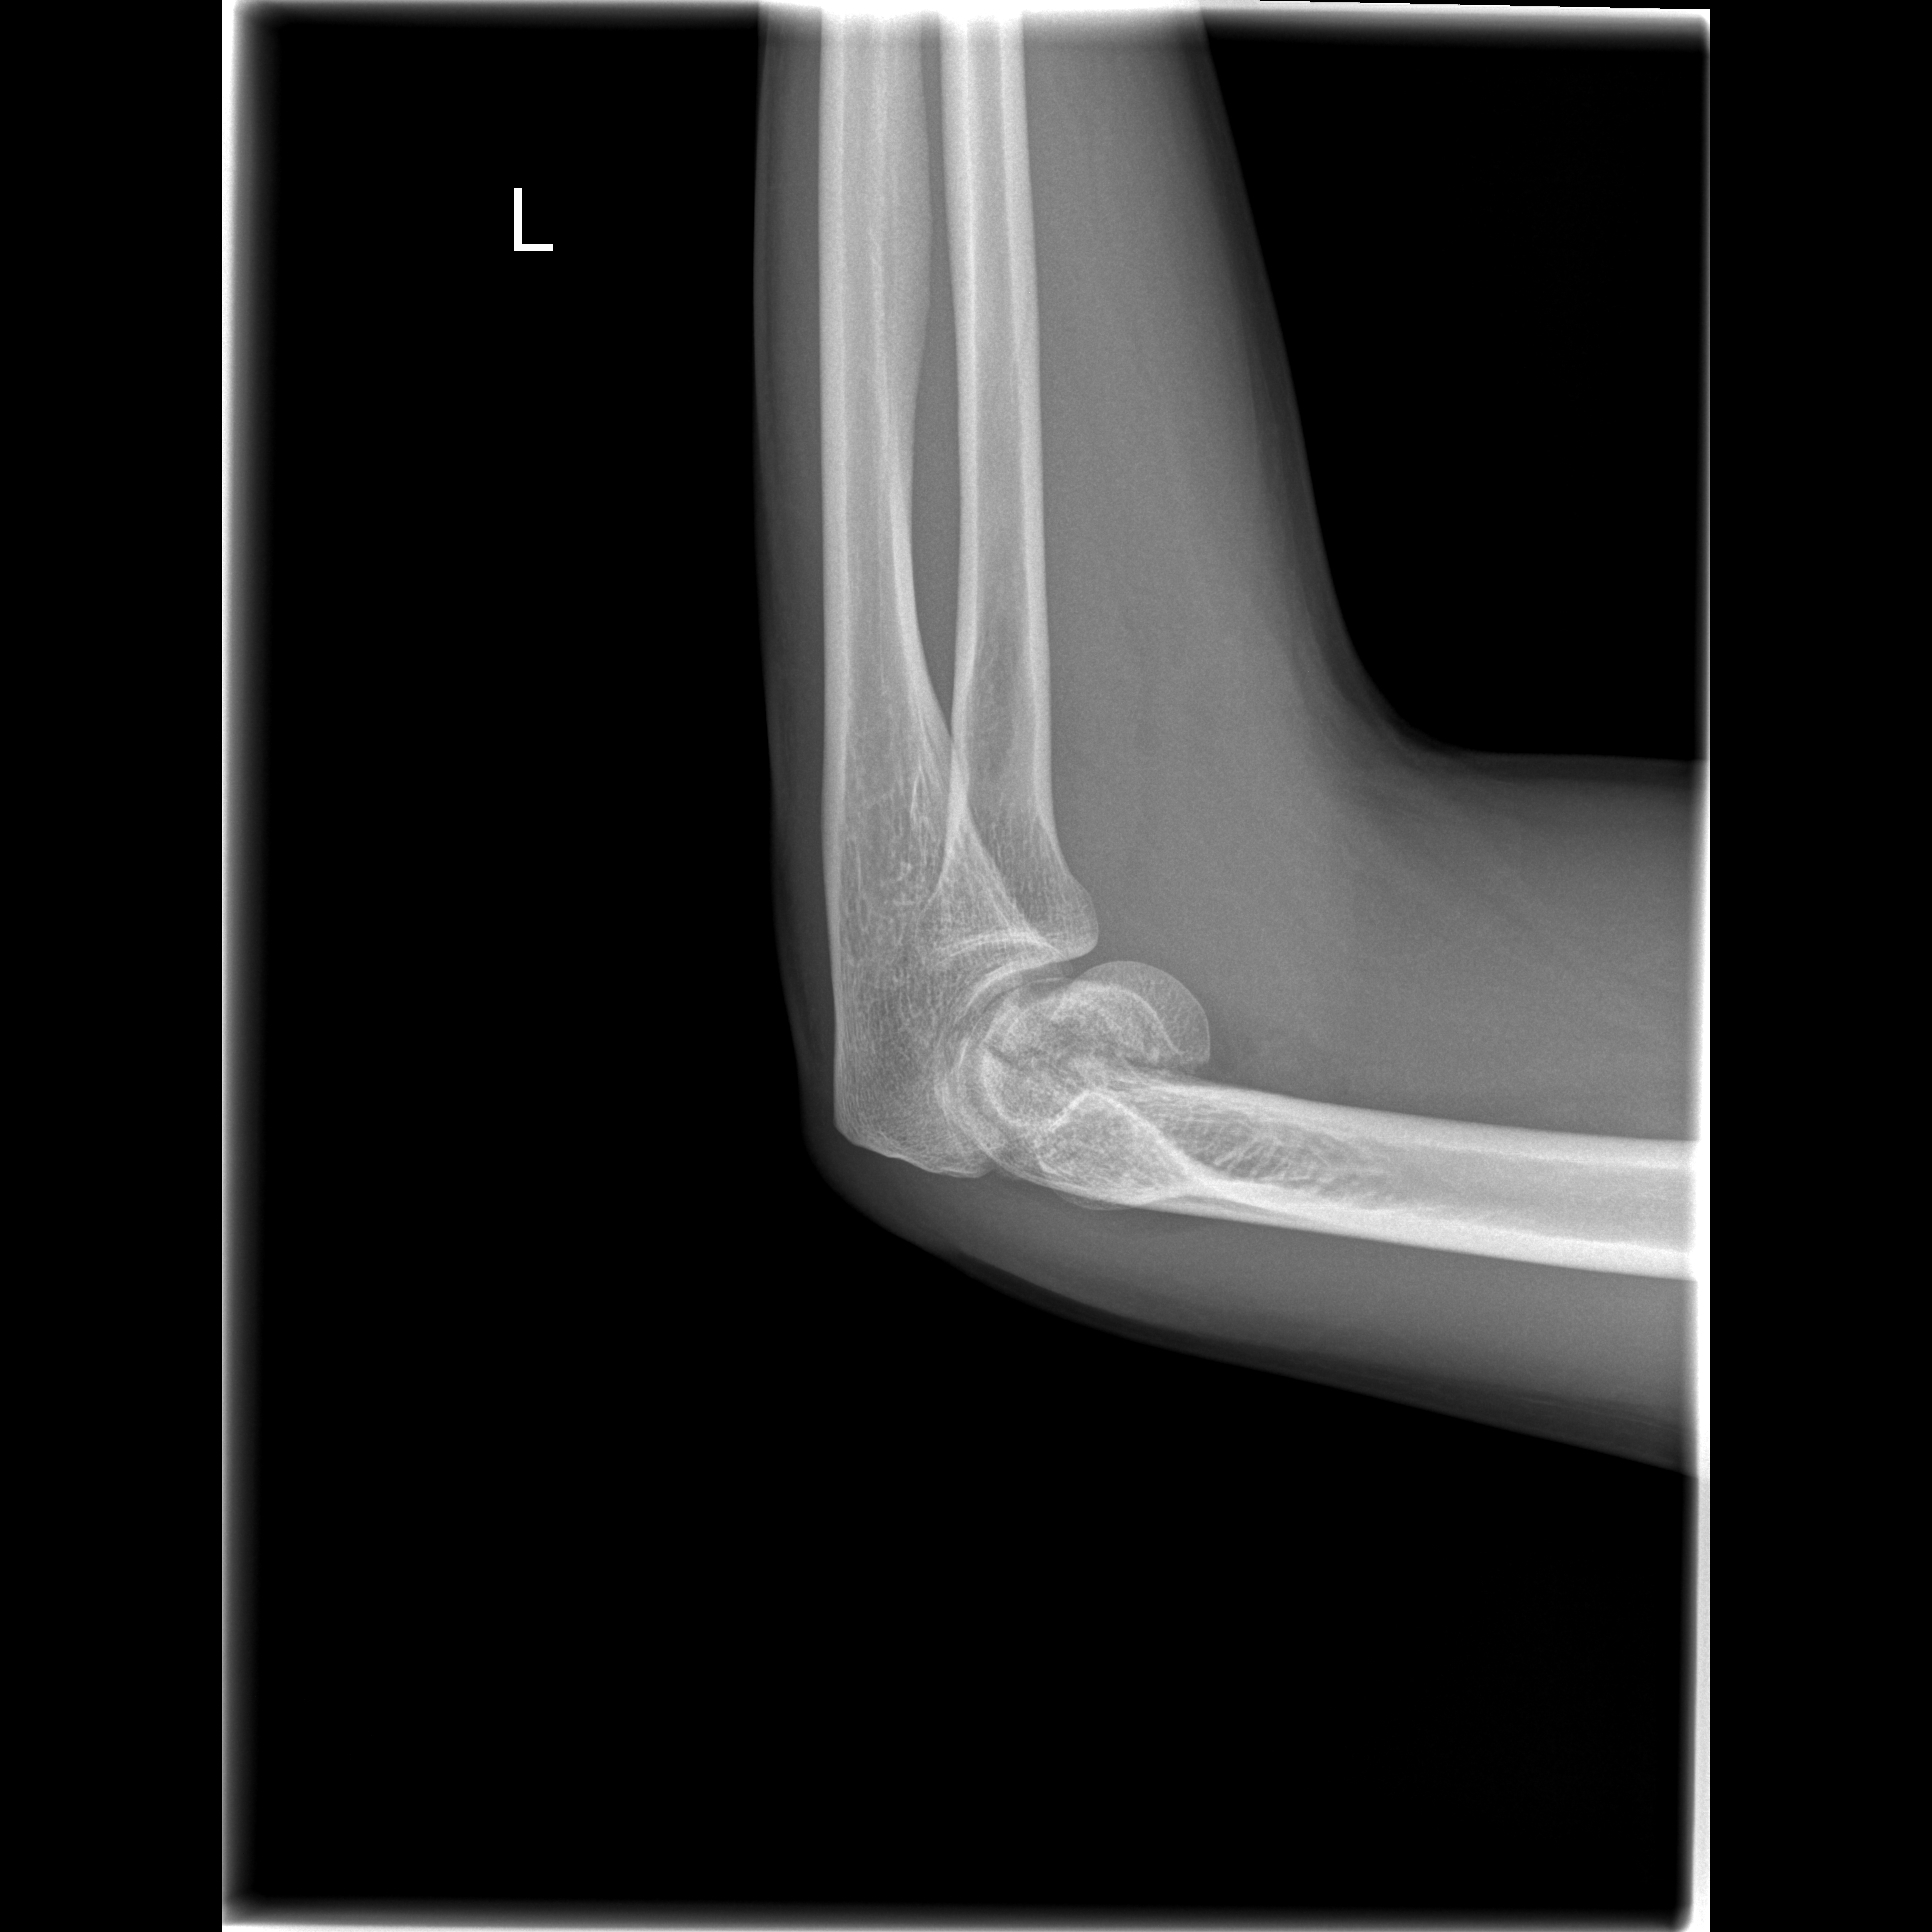

We will start explaining what a CT scan is. CT stands for Computed Tomography and is an imaging technology based on X-rays. X-rays are a type of light with very high energy. Most objects are translucent in this light, that is to say, they allow the light to pass although they might absorb part of it. Bones, for example, absorb more X-ray light than other tissues. For this reason, X-rays are used to take pictures of what is inside our body. If you have ever received an X-ray for a fractured bone, the doctor often will take two images, so that each of the two images show everything inside us from a different perspective. Certain features that may appear in the same spot in one of the images (for example a bone hiding behind a different bone), will be separated in the other one. With both these images, a physician may have a better understanding of what is happening than with a single one. If we increase the number of images we take, such as if we took three images instead of two, we could differentiate even better the spatial distribution of our insides. If we take this approach a step beyond and take an X-ray image from every possible angle in a 360 degree circle around the patient, then we would know perfectly the shape and location of every organ in our patient’s body. With all this information, it is possible to use a Computer (the C in CT) to transform this set of images into a single 3D image. This is the fundamental operation of a CT scan.